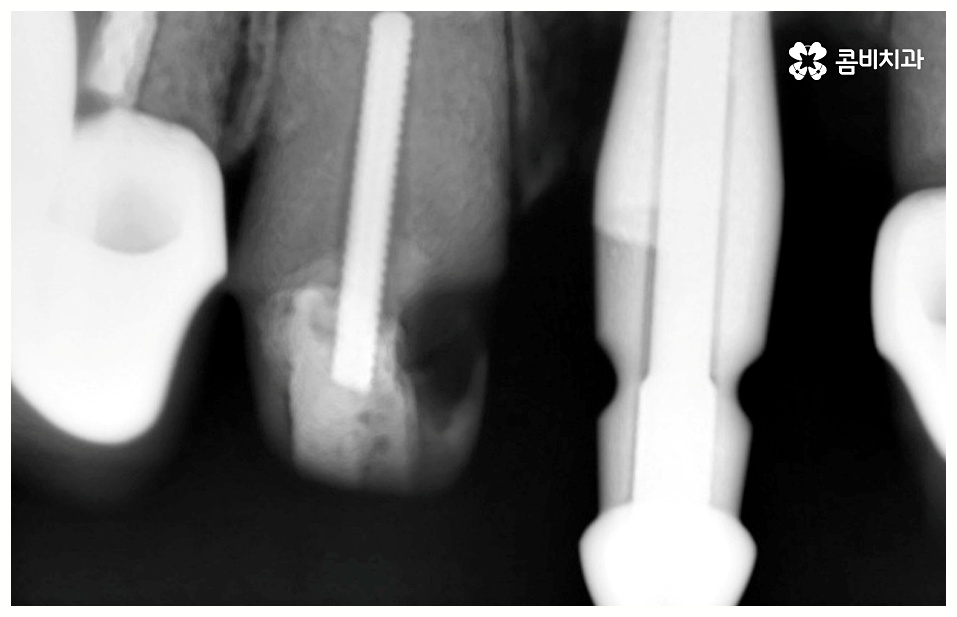

예를 들어서 잇몸뼈가 튼튼하다면 발치 후 즉시 임플란트 식립 시술을 할 수 있어서 임플란트 치료기간 이 줄어들고 보다 간편한 수복이 가능할 것이나 주변 잇몸에 염증이 남아있어서 먼저 치료를 해야 하거나 바탕이 되는 잇몸뼈의 밀도, 높이 등이 부족하여 보충이 필요한 경우에는 뼈이식 과정을 우선 진행해야 하기 때문에 임플란트 치료기간 이 길어질 수 있어요.

뼈이식은 각자에게 맞는 골이식재료 가루를 생리식염수에 반죽하여 빈 공간에 채워넣으면 이를 이용하여 우리의 세포가 잇몸뼈를 만들어내는 골융합 과정을 의미하는데 회복 시간을 충분히 주어 무리가 가지 않도록 진행을 해야 안정성과 지속성을 높일 수 있기 때문에 임플란트 치료기간 자체를 줄이는 데 초점을 맞추는 것보다는 필요한 처치들을 꼼꼼하게 해 주는 것에 초점을 맞추시는 게 필요할 거예요.